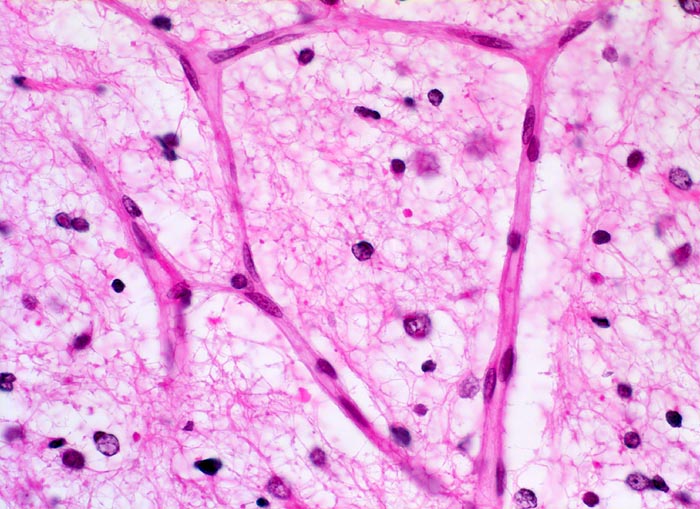

Histologisch bestehen die Oligodendrogliome aus kompakten Aggregaten runder Zellen mit deutlichen Zellgrenzen und klarem Zytoplasmasaum um einen dichten runden zentralen Kern (“Spiegelei”). Die Vakuolisierung des Zytoplasma stellt einen Fixationsartefakt dar und fällt bei Schnellschnitten als diagnostisches Hilfsmittel weg (Gefrierschnitt!). Charakteristisch sind verzweigte Kapillaren. Die Tumorzellen infiltrieren die Hirnrinde diffus und können sich bis in die Meningen ausbreiten.

• Fokale mukoide/zystische Degeneration innerhalb des Tumors mit Ausbildung von Pseudozysten.

• Dichtes Netzwerk verzweigender Kapillaren.

• Tumorzellen umgeben von einem Halo ("Spiegeleier").

• Die Tumorzellen erinnern an Oligodendrozyten der weissen Substanz, haben aber deutlich grössere Kerne.